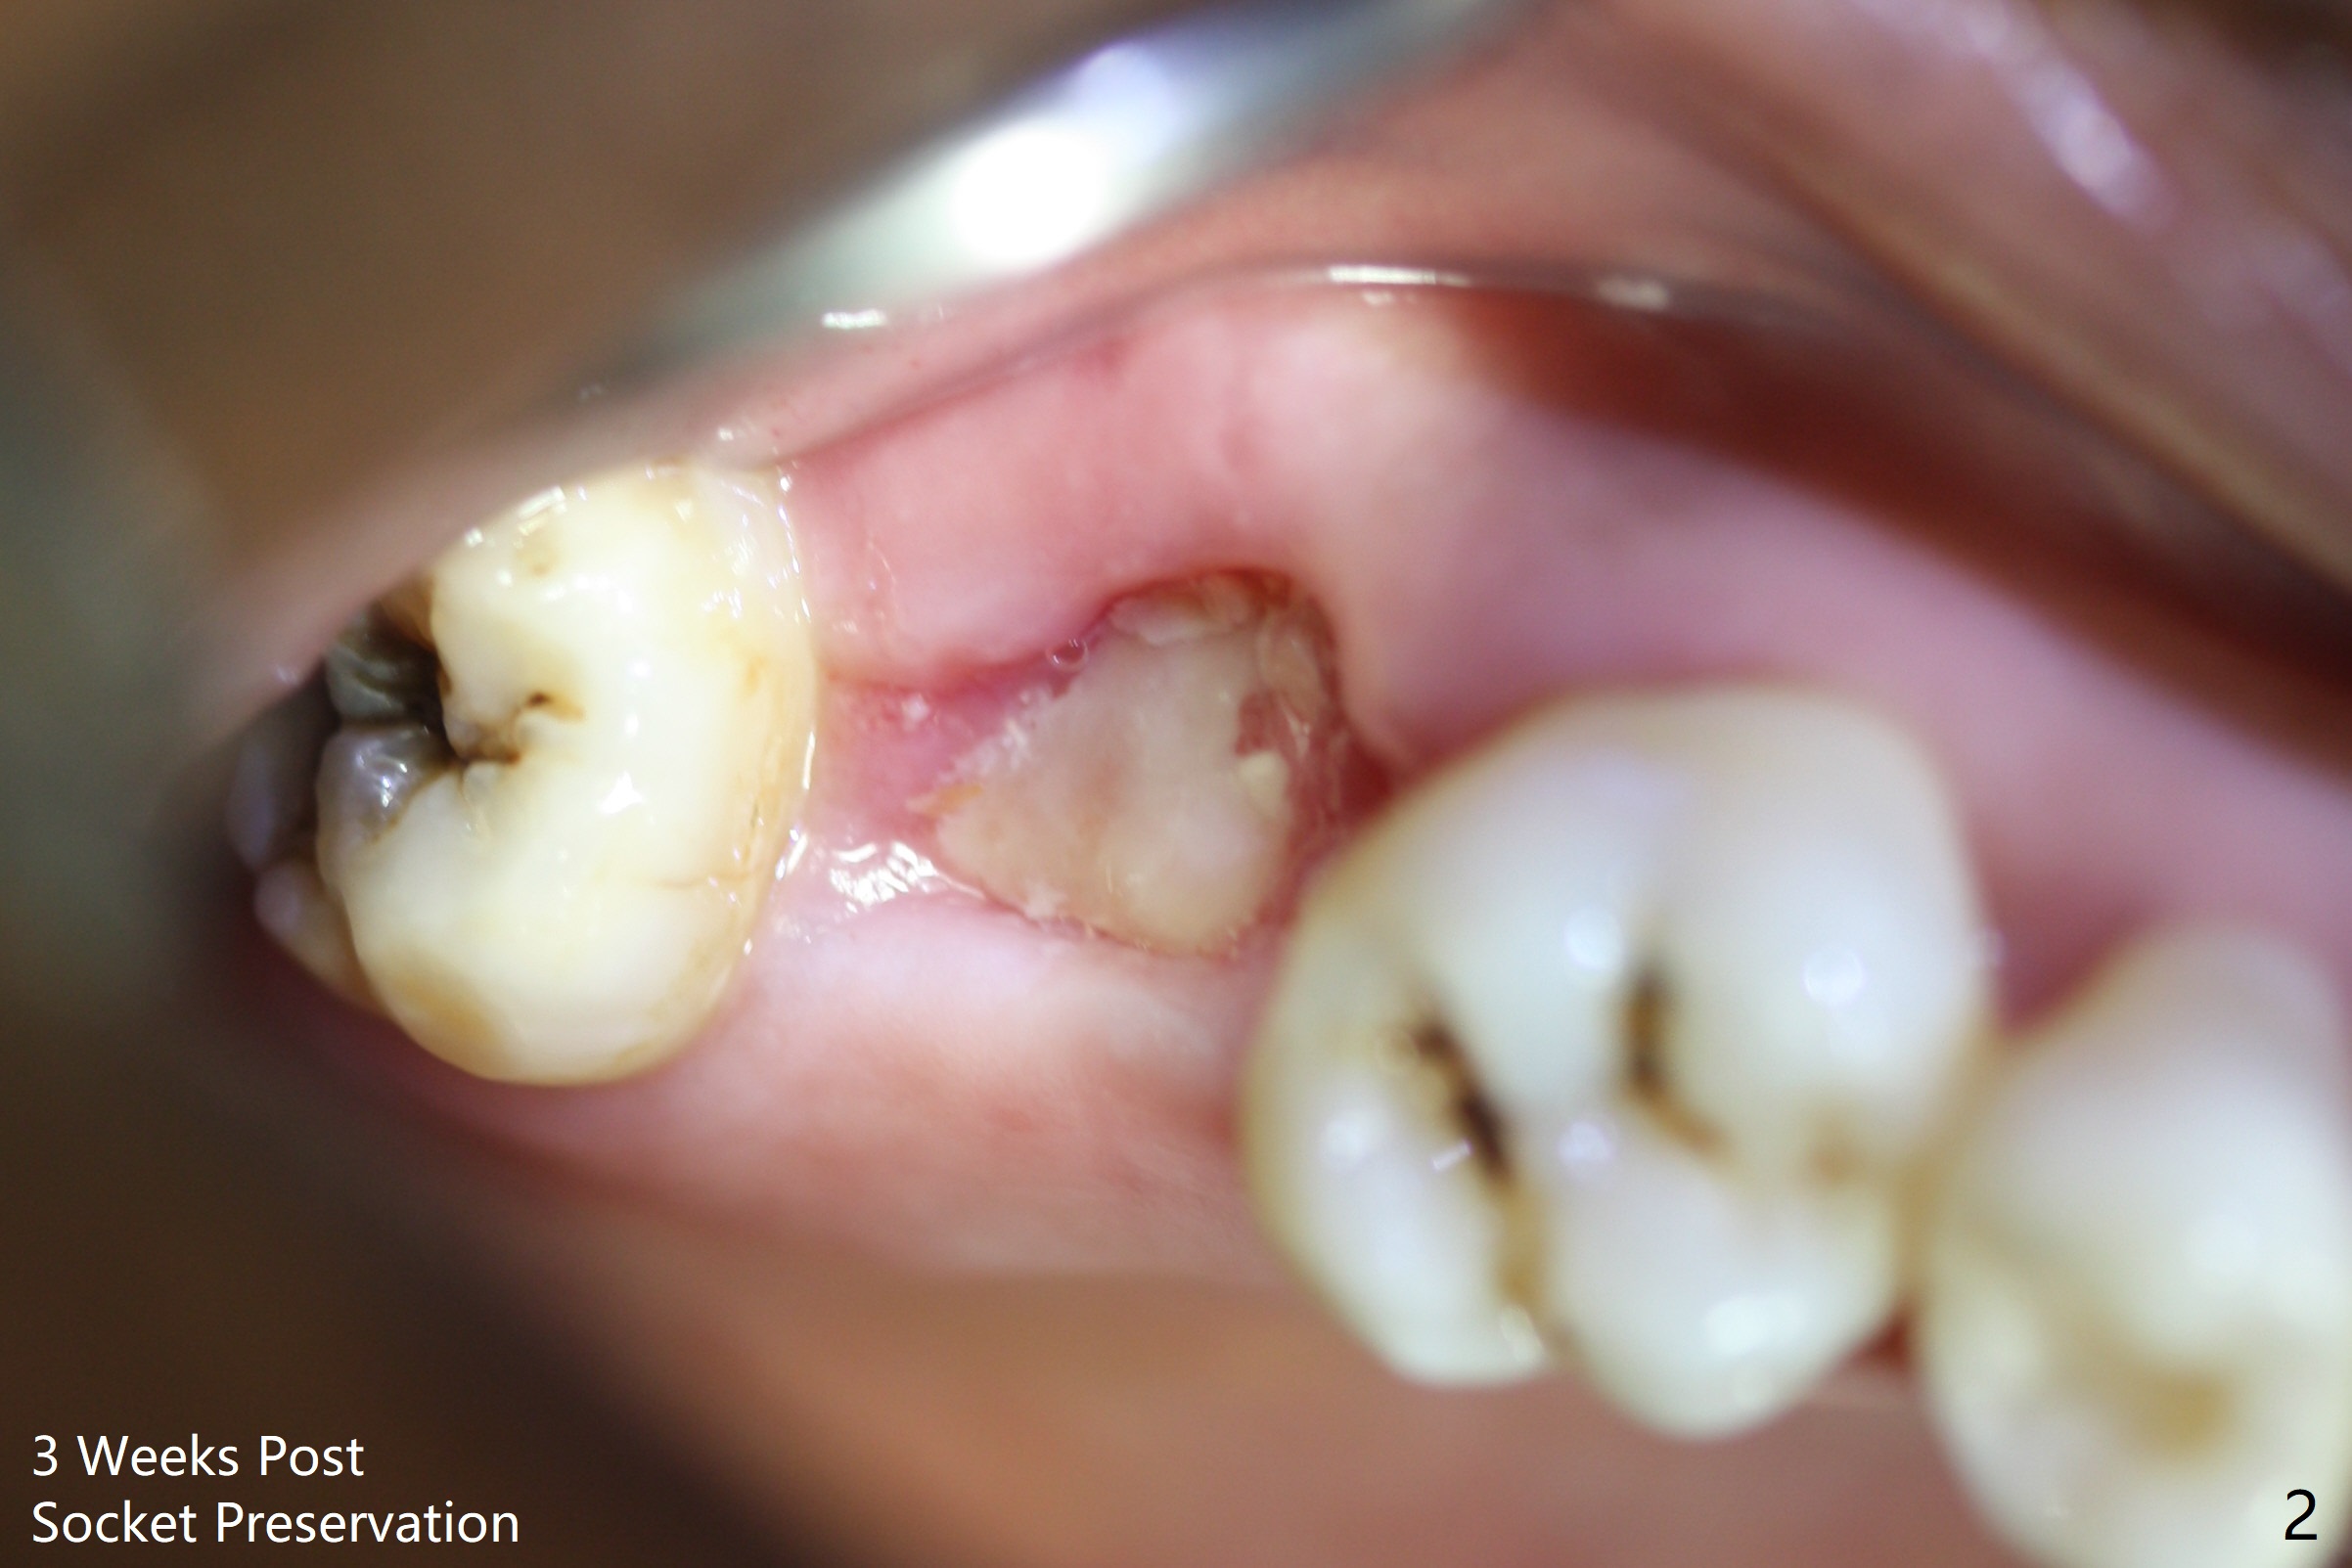

A 49-year-old woman, a dental phobic, refuses RCT for the tooth #2 (Fig.1) and agrees with extraction. With socket preservation with allograft and Osteogen plug, the socket heals in 3 weeks (Fig.2).